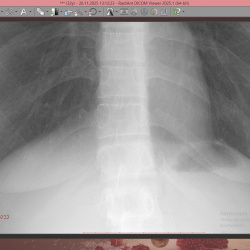

Здравствуйте,пациентке назначена рентгенография Пояснично-кр отд п-ка,1948 гр,случайная находка,что за тень?смещается при повороте